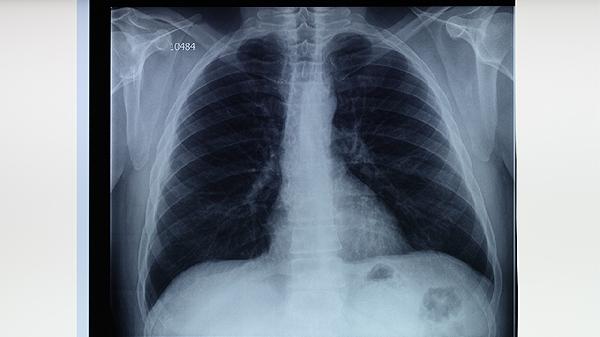

原發(fā)性肺結(jié)核的診斷主要依據(jù)胸部影像學(xué)檢查和結(jié)核菌素試驗(yàn)。胸部X線或CT可見(jiàn)肺內(nèi)原發(fā)病灶和肺門淋巴結(jié)腫大,形成啞鈴狀陰影。結(jié)核菌素試驗(yàn)陽(yáng)性有助于診斷,但需結(jié)合臨床表現(xiàn)和其他檢查結(jié)果綜合判斷。痰涂片找抗酸桿菌和痰培養(yǎng)檢查可幫助確診,分子生物學(xué)檢測(cè)如GeneXpert檢測(cè)可快速診斷結(jié)核分枝桿菌感染。